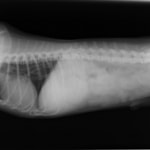

11歳 ミニチュア・ダックス 去勢オス

主訴:焼き鳥の竹串を食べたとの事で来院しました。元気・食欲は問題なく、嘔吐などの症状もありませんでした。便にも竹串が1/3程でているとの事でしたが、全ての竹串が出ていないため、内視鏡検査を実施致しました。